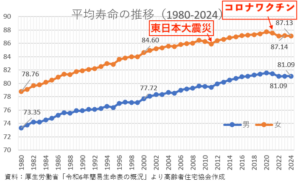

新型コロナワクチン接種による妊娠への影響